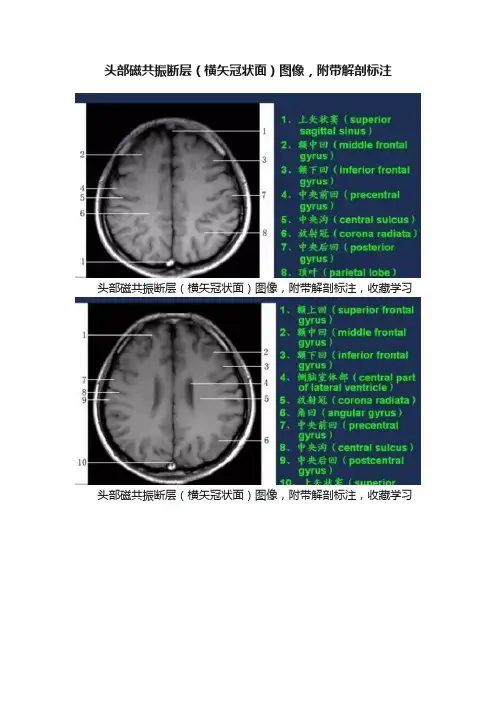

头部磁共振断层(横矢冠状面)图像,附带解剖标注

头部磁共振断层(横矢冠状面)图像,附带解剖标注,收藏学习